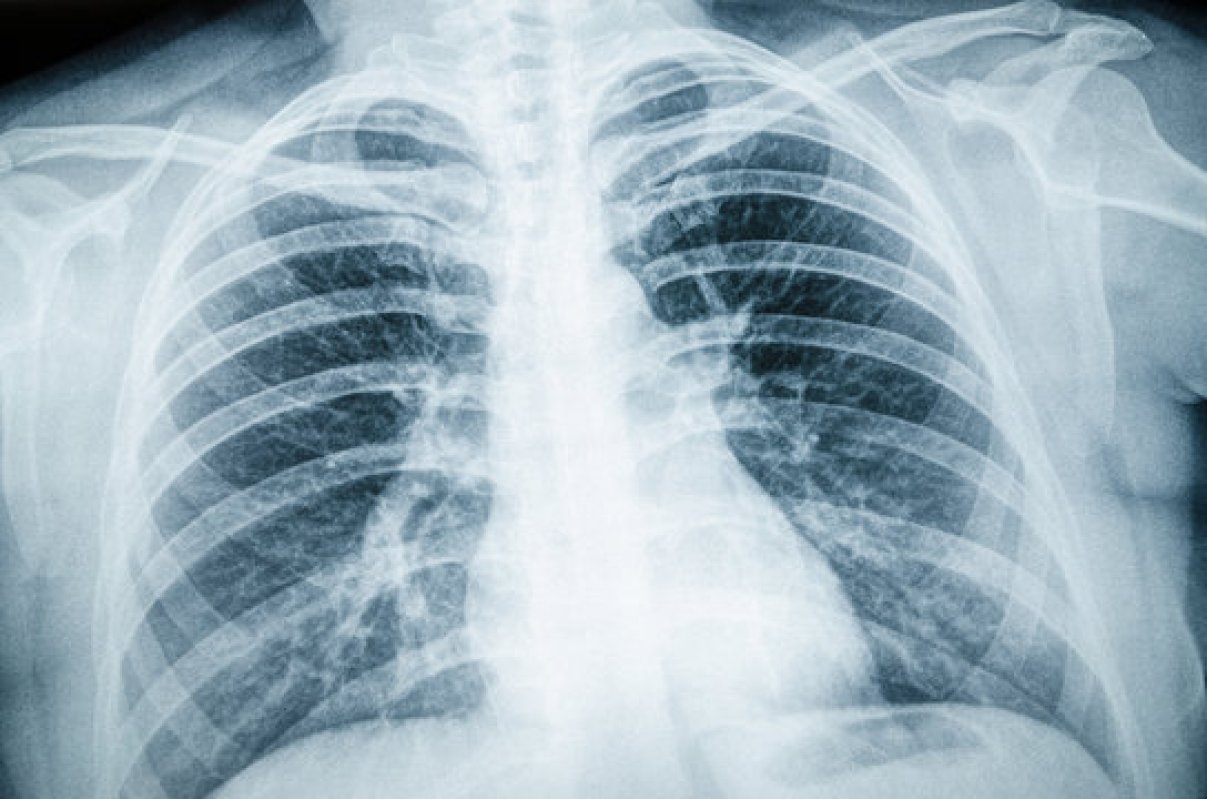

Флюорографія — це одне з найпоширеніших та найшвидших обстежень у медицині, яке дозволяє перевірити стан легень і грудної клітки. Для багатьох пацієнтів вона здається просто формальністю для довідки на роботу чи навчання. Насправді ж цей знімок здатен виявити серйозні захворювання ще до того, як вони дадуть перші симптоми. Сьогодні використовується цифрова флюорографія — сучасна технологія, яка суттєво відрізняється від старих плівкових методів.

Цифрова флюорографія — це різновид рентген-обстеження грудної клітки, коли зображення отримують і обробляють у цифровому форматі. На відміну від старої плівкової технології, цифрові системи дають більш чітку картинку при меншій дозі випромінювання. Лікарі одразу бачать знімок на екрані, можуть збільшити фрагменти, підкрутити контраст, порівняти з попередніми дослідженнями — усе це підвищує точність висновку.

Простими словами, це «розумний рентген легень», який робиться швидко, зручно та безпечно.